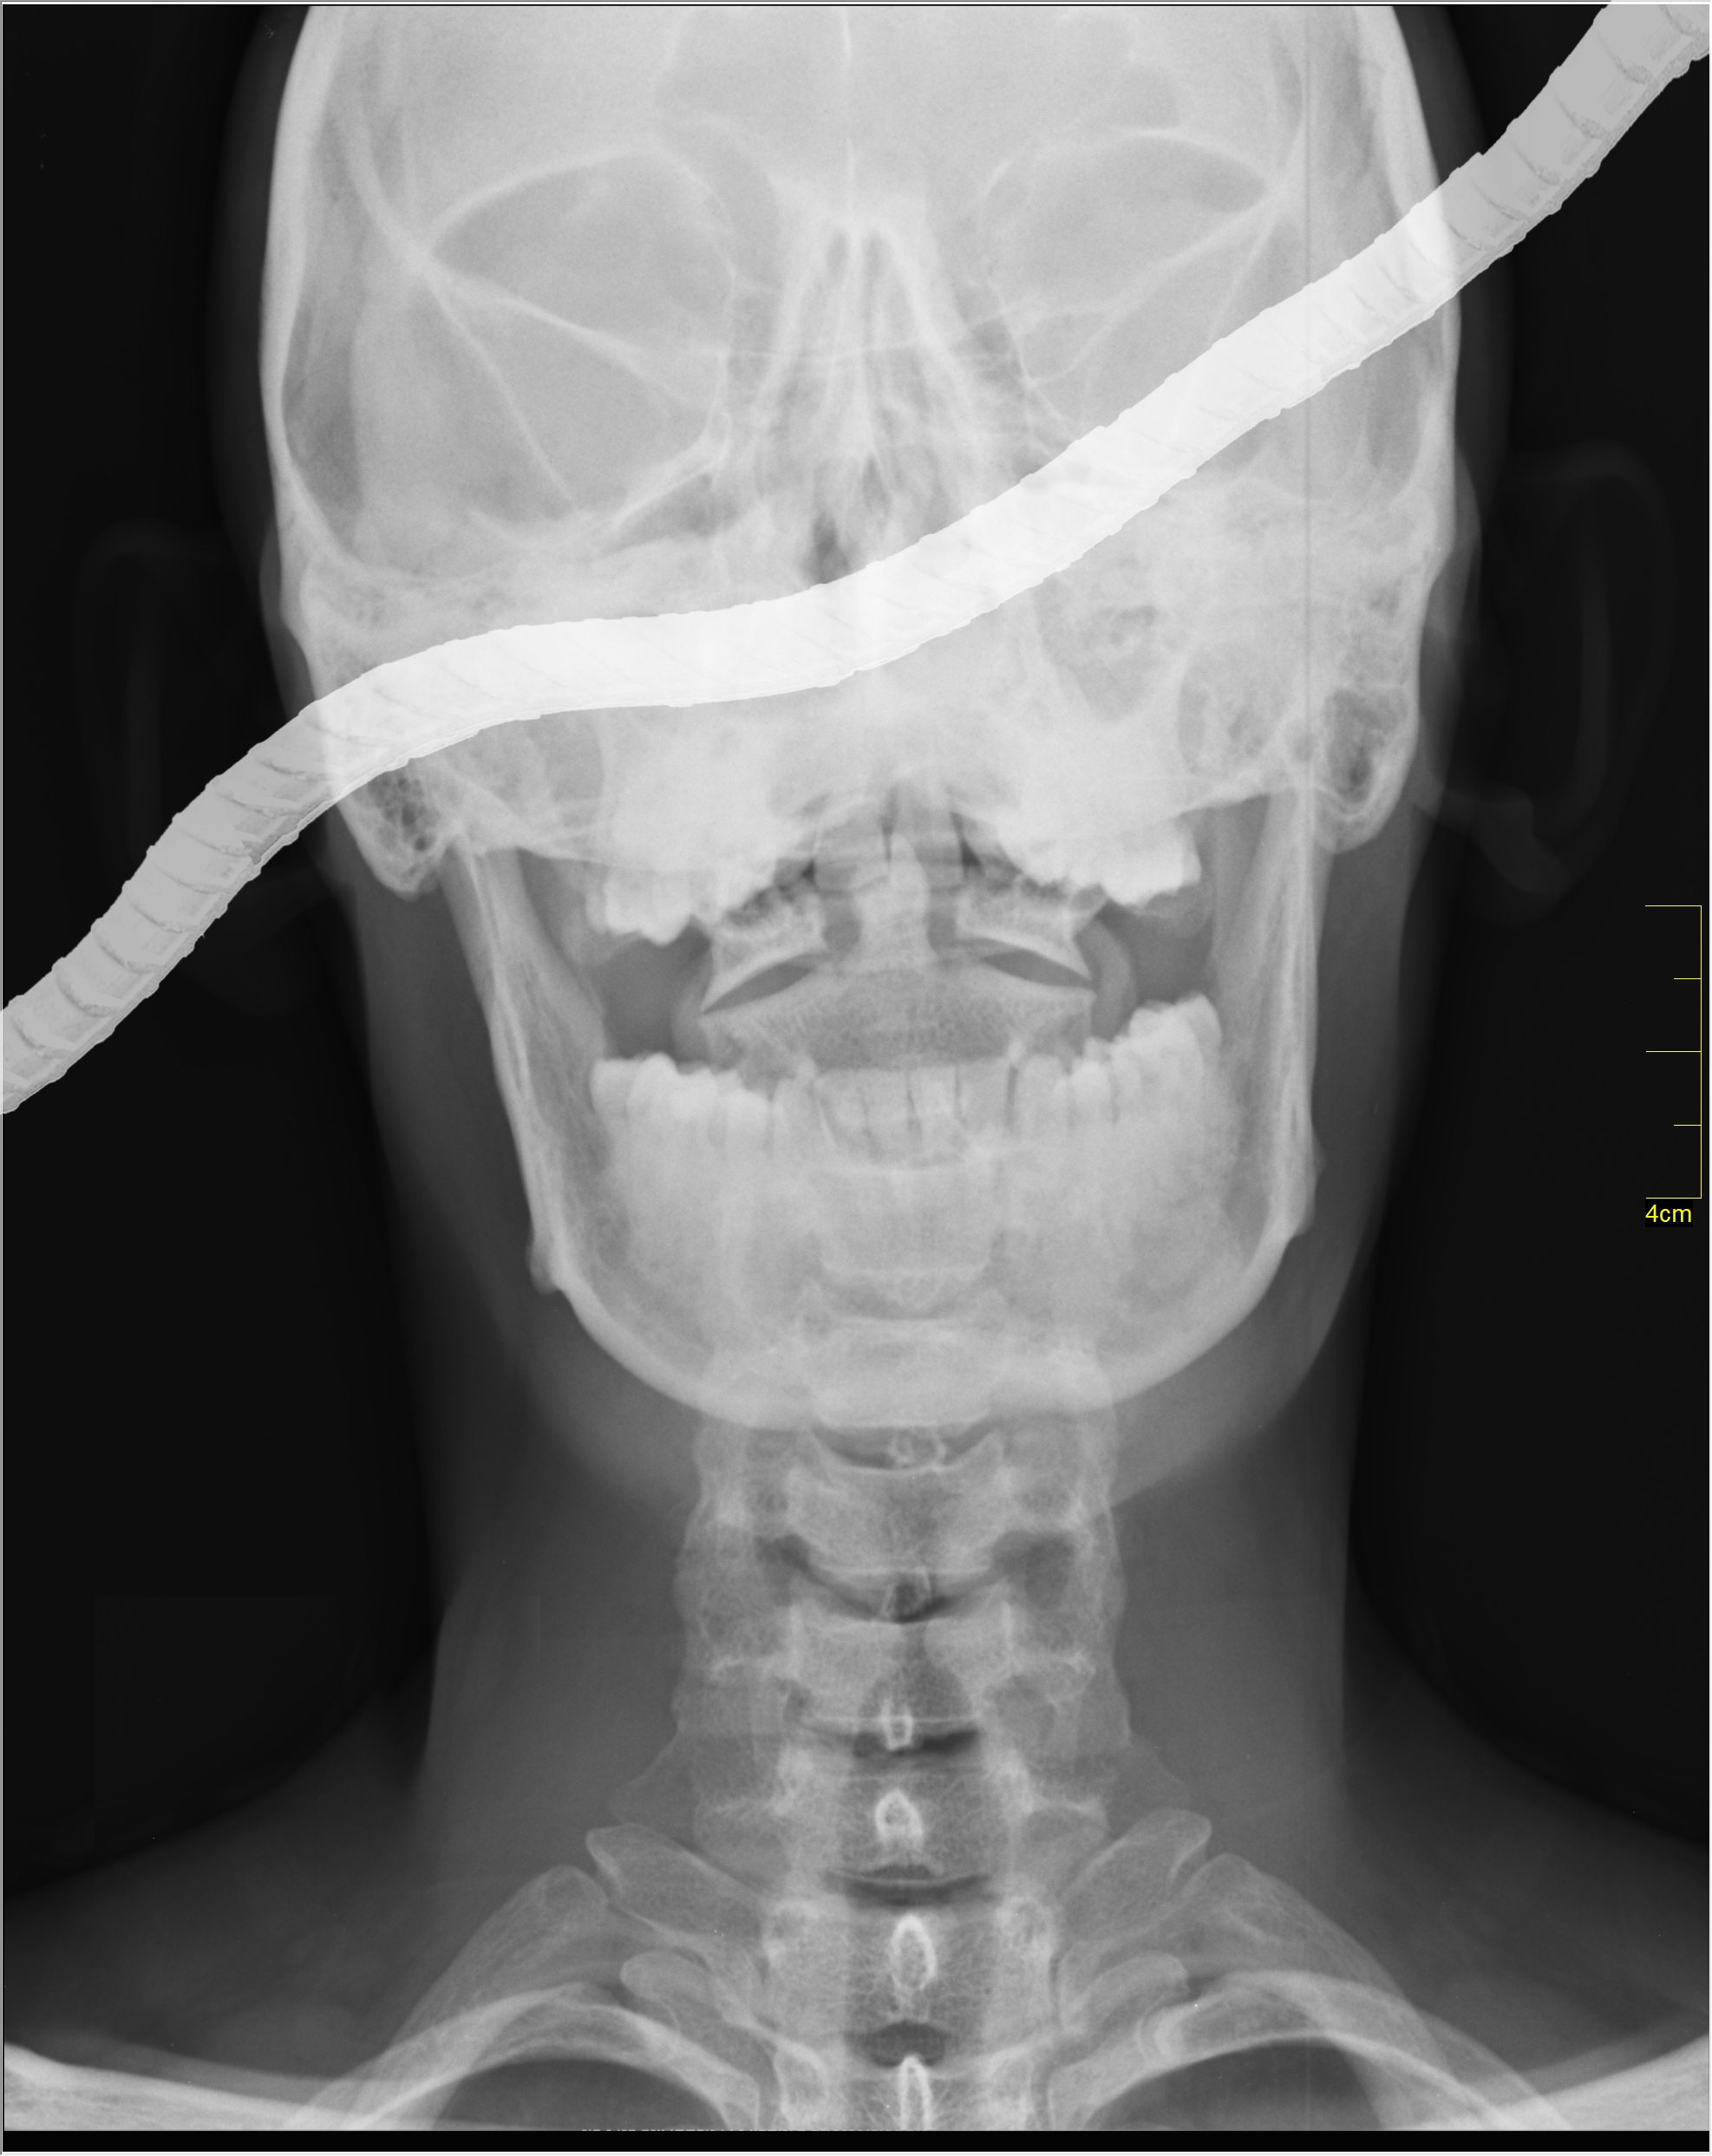

特工M████死亡后X光照片。可明显看到SCP-024-IT个体(已无效化)。